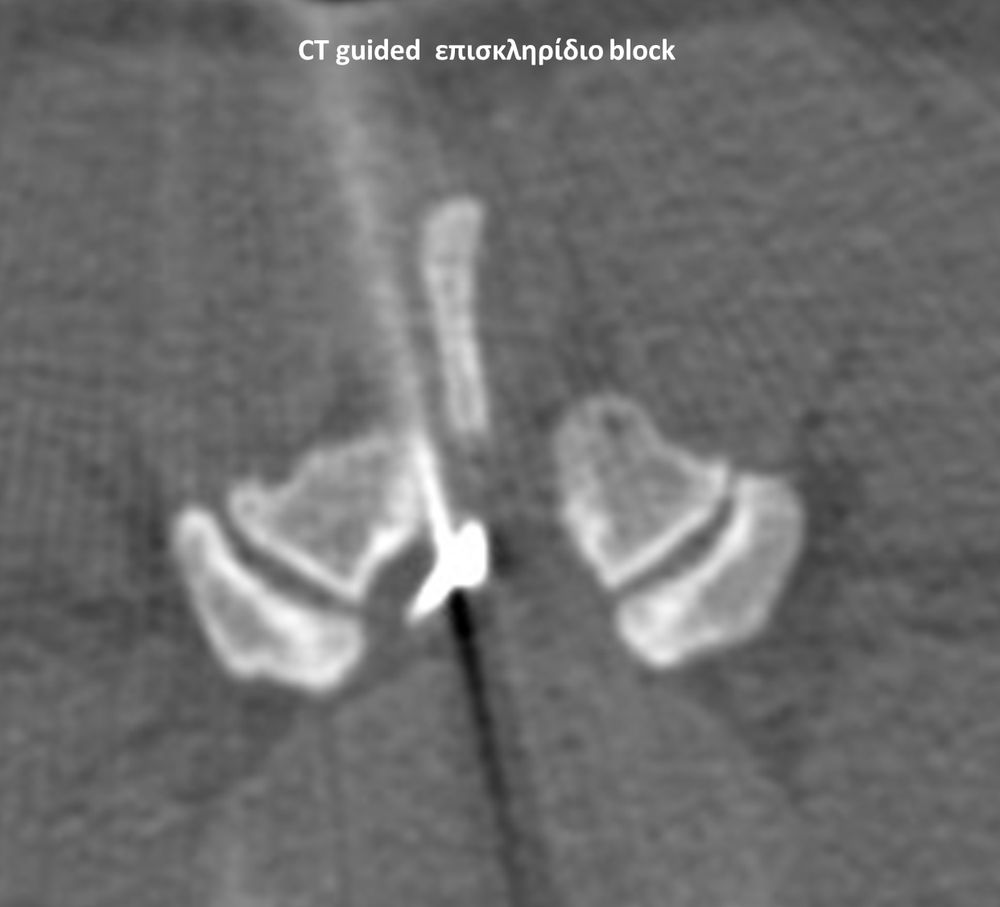

Με την βοήθεια της επεμβατικής ακτινολογίας είναι δυνατόν να πραγματοποιηθούν διαφορες ενέσιμες τεχνικές που αποσκοπούν στη μείωση του μυοσκελετικού πόνου, την ενίσχυση της αποτελεσματικότητας της φυσιοθεραπείας και την επιτάχυνση της διαδικασίας επούλωσης. Οι τεχνικές αυτές περιλαμβάνουν την κατευθυνόμενη έγχυση φαρμάκων ή πραγματοποίηση θεραπευτικών χειρισμών ακριβώς στη θέση τηςπαθολογία. Ετσι εξασφαλιζεται η μέγιστη αποτελεσματικότητα ( έως 95% κατά περίπτωση) και ασφάλεια σε σχέση με τυφλούς χειρισμούς χωρίς ακτινολογική καθοδήγηση.